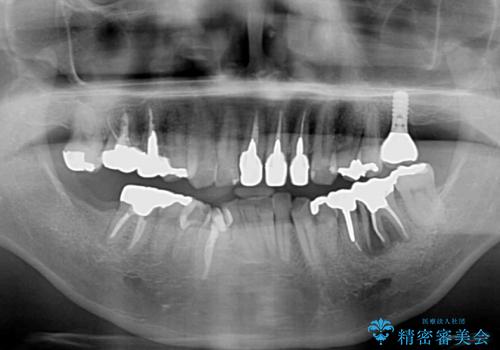

欠損している歯や、割れてしまって抜歯の必要な歯などがあり、咬合力が強いため欠損部はインプラント補綴を前提に治療を行うこととしました。

しかしながら、左下の抜歯部位は骨欠損が著しく大きく、多大な垂直的骨造成を要するため、3歯を支台としたブリッジによる補綴治療とし、右下のみをインプラント補綴としました。

小さい修復物の銀歯が装着されている歯はセラミックインレーにて、その他はオールセラミッククラウンにて補綴治療を進めることとしました。